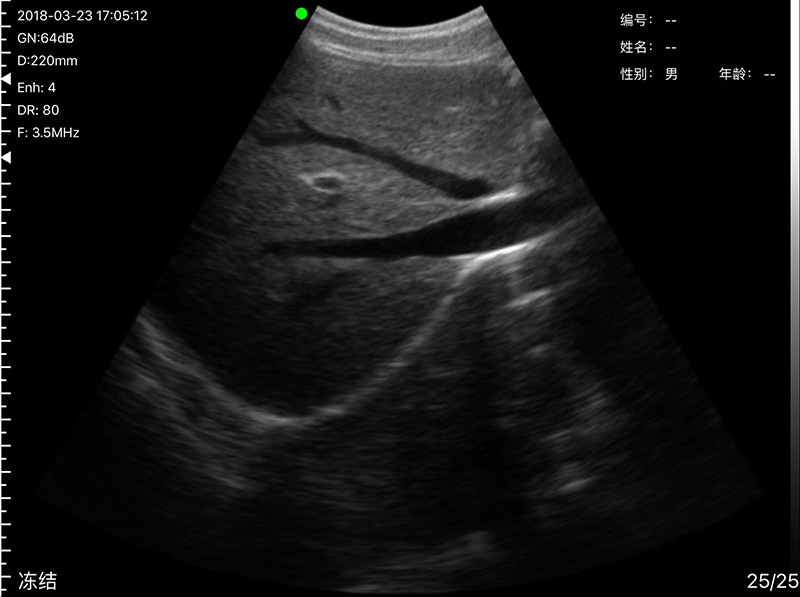

• Probe Head: R60 Convex+R13 Transvaginal

• Display mode: B, B/M, color doppler version with B+Color, B+PDI, B+PW

Convex head 3.2MHz/5MHz, 90/160/220/305mm, R60